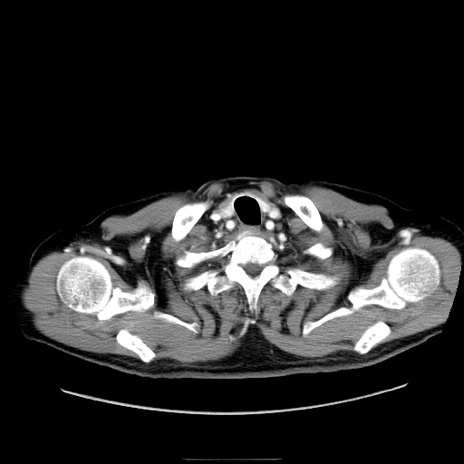

症例30(横断像)

【症例】80歳代男性

【主訴】臍周囲痛

【現病歴】約6時間前から臍下部痛が出現。次第に腹部膨隆・背部痛も生じてきたため来院。背部痛の場所は変化しない。

【既往歴】腎盂腎炎

【身体所見】意識清明、BT 36.3℃、BP  131/87mmHg、P 87bpm、SpO2 100%(RA)、臍周囲自発痛・圧痛あり、反跳痛なし、自発痛部位に一致して板状硬あり、腹部膨隆、腸雑音減弱、CVA tenderness両側陰性。

【データ】WBC 19600、CRP 0.33